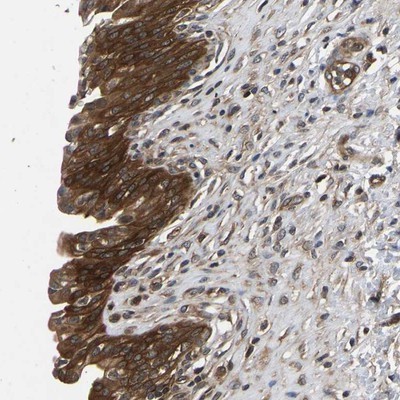

- Main image

- Experimental details

- Immunohistochemistry-Paraffin: FGD5 Antibody [NBP1-83877] - Staining of human urinary bladder shows strong cytoplasmic positivity in urothelial cells.